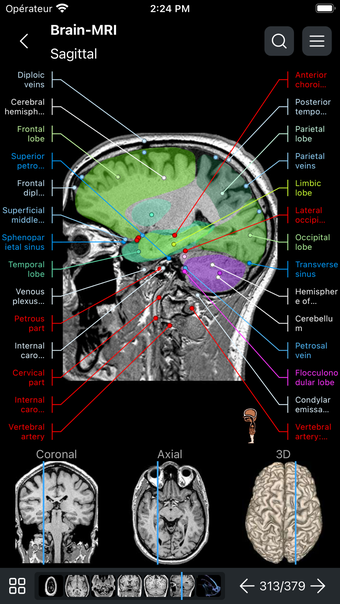

IMAIOS e-Anatomy es un atlas en línea de anatomía humana para médicos, enfermeras, estudiantes de medicina y técnicos en radiología. Utiliza IMAIOS e-Anatomy en tu smartphone o tablet para encontrar la ubicación de cualquier condición médica o estructura anatómica. El detallado e-Anatomy te proporcionará una referencia de acceso rápido de la anatomía humana y sus principales órganos y funciones.

Encuentra la ubicación de cualquier condición médica o estructura anatómica con IMAIOS e-Anatomy en tu smartphone o tablet. Busca enfermedades, anatomía y estructuras anatómicas, e incluso ve la ubicación de todos los puntos de referencia anatómicos. Puedes encontrar la ubicación de cualquier estructura o condición anatómica con la información médica detallada, fácilmente ingresando los detalles anatómicos relevantes.

Encuentra la ubicación de cualquier estructura o condición anatómica con IMAIOS e-Anatomy en tu smartphone o tablet. Utiliza la guía de anatomía para encontrar la ubicación de las estructuras anatómicas, enfermedades y trastornos, e incluso la anatomía y estructura de los dedos y manos.

IMAIOS e-Anatomy es un atlas médico. Utilízalo como referencia médica para averiguar dónde se encuentra cualquier condición médica o estructura anatómica en el cuerpo humano.

IMAIOS e-Anatomy es un atlas en línea de anatomía humana. Proporciona información médica detallada sobre la anatomía y estructura del cuerpo humano. Utiliza IMAIOS e-Anatomy en tu smartphone o tablet para encontrar la ubicación de cualquier estructura o condición anatómica.